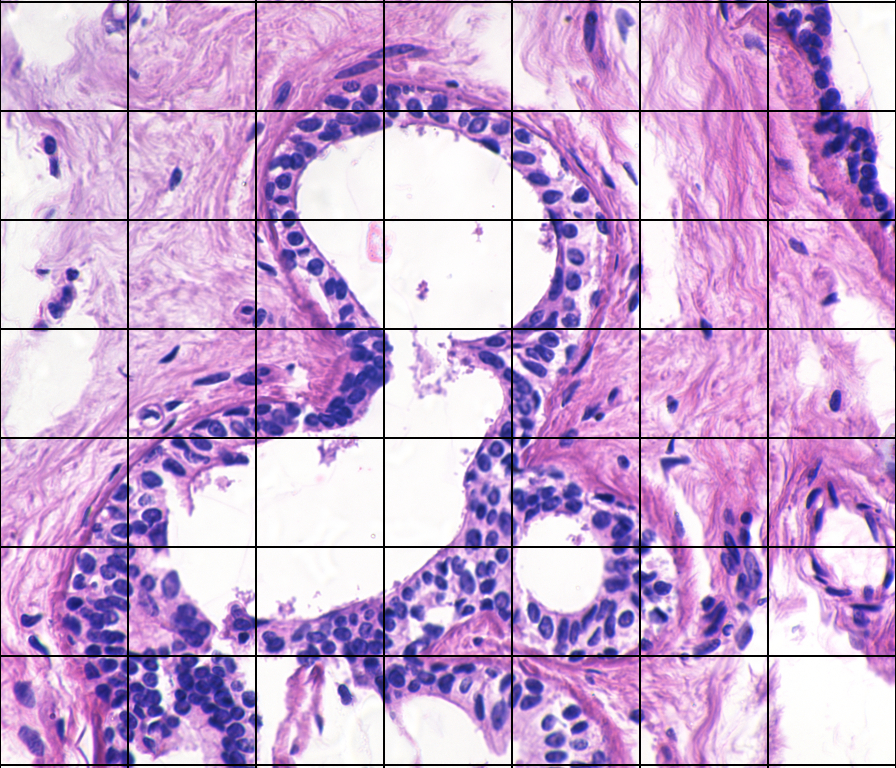

Figure 1a shows an image (bag), k𝑘k, of benign breast tissue [1], divided into nksubscript𝑛𝑘n_{k} segments with corresponding feature vectors (instances) 𝐱k1,,𝐱knksubscript𝐱𝑘1subscript𝐱𝑘subscript𝑛𝑘\mathbf{x}_{k1},\ldots,\mathbf{x}_{kn_{k}} [2]. Correspondingly, figure 1b shows malignant breast tissue.

(a) Benign

(b) Malignant

Figure 1: Breast tissue images. The image segments are not labelled.

The images in the data set have class labels, the individual segments do not. This is a key characteristic of MI learning: the instances are not labelled. MI learning includes instance classification [3], clustering [4], regression [4], and multi-label learning [5, 6], but this article will focus on bag classification. MI learning can also be found as integrated parts of end-to-end methods for image analysis that generate patches, extract features and do feature selection [6]. See also [7] for an overview and discussion on end-to-end neural network MI learning methods.

Breast tissue images (see Fig. 1) with corresponding feature vectors are used as example. Following the procedure in [2], the principal components are used for dimension reduction, and 444-fold cross-validation is used so that f^neg(x)subscript^𝑓𝑛𝑒𝑔𝑥\hat{f}_{neg}(x) and f^pos(x)subscript^𝑓𝑝𝑜𝑠𝑥\hat{f}_{pos}(x) are fitted only to the instances in the training folds. For pdf estimation, GMMs are fitted to the first principal component, using an EM-algorithm, with number of components chosen by minimum AIC. In addition, KDE as in Section 5.1, and KDE with Gaussian kernel and optimal bandwidth [41] is used.